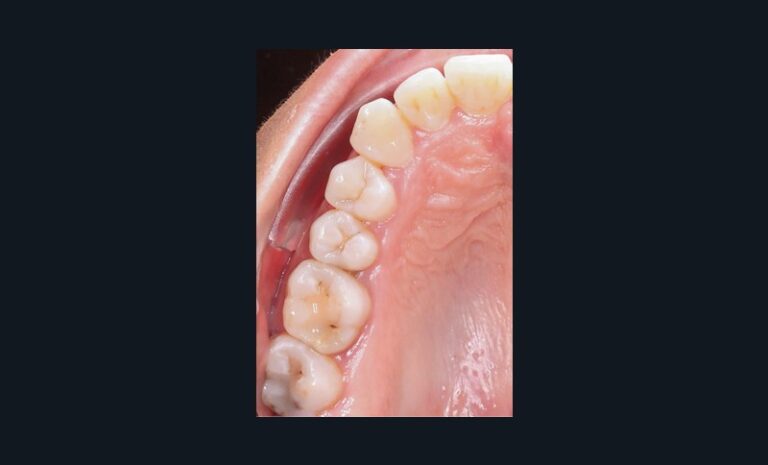

Dans l’exemple (fig. 1 et 2), la patiente présente une classe 1 molaire et classe 2 canine bilatérale sur un schéma normodivergent de classe 2 squelettique associé à une biproversion incisive et la canine 23 incluse.

Avec les aligneurs que je programme, la première phase de traitement consiste en un stripping de 0,5 mm de mésial molaire à distal canine afin de permettre une distalisation des prémolaires et canines pour obtenir un gain possible de 1,5 mm en mésial des canines avant l’étape d’alignement incisif.